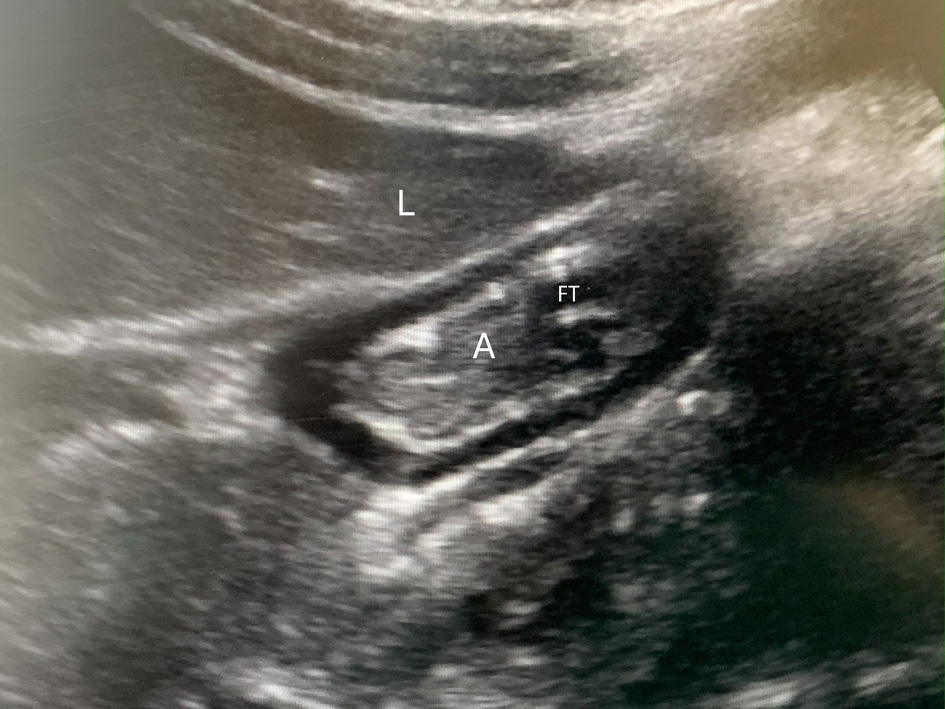

Proper placement of the feeding tube (NG or NJ) was confirmed on the morning radiograph. Ultrasound studies were obtained up to three times on each patient on different days, based on availability of the authors trained in POCUS. Gastric ultrasound was performed in the pediatric ICU by an investigator proficient in diagnostic POCUS. A Sonosite X-Porte (Sonosite Inc. USA) machine with a low frequency (3–8 MHz) curvilinear probe was utilized. The ultrasound was performed with the child lying in the supine position followed by the right lateral decubitus (RLD) position. In situations where it was not feasible to place the patient in the right lateral decubitus position, the patient was placed in a 45° semi-recumbent position. The gastric antrum was identified in a sagittal plane between the left lobe of the liver and the pancreas at the level of the descending aorta and superior mesenteric artery (Fig. 1) [10]. Qualitative and quantitative measurements of the gastric antrum were recorded. The quantitative exam was performed using the cross-sectional area of the gastric antrum. The cross-sectional area (CSA) of the antrum was measured with a free-tracing method to follow the outer margin of the antrum corresponding to the serosal layer. The gastric volume was calculated using the following formula: Gastric volume (mL/kg) = [−7.8 + 0.035 × CSA (mm2) + 0.127 × age (months)]/body weight (kg)]. The qualitative and quantitative measurements were performed using a three-point grading scale as described by Spencer et al [6]. Grade 0 includes no fluid visible in the gastric antrum; grade 1 includes clear fluid visualized with volume less than 1.5 mL/kg; and grade 2 includes clear fluid visualized with a volume ≥ 1.5 mL/kg. A high risk of aspiration was defined as grade 2 or the presence of any solid or thick liquid on exam.

Figure 1. Gastric ultrasound in a patient receiving post-pyloric feedings via feeing tube (FT) showing the collapsed antrum (A) with the classic “bull’s eye appearance,” positioned under the liver (L).